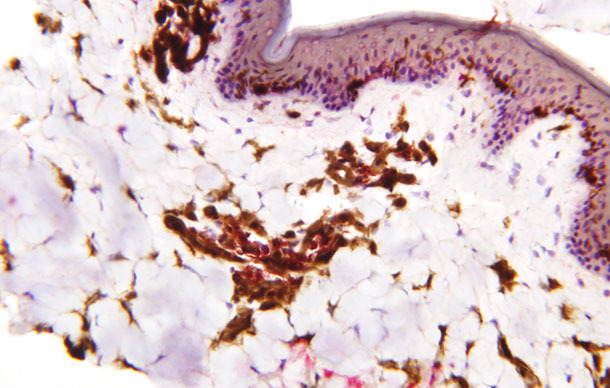

Figure 2 : Répartition des cellules dendritiques dans l’épiderme, le derme et le tissu sous-cutané chez le porc. Les cellules dendritiques sont colorées en marron (Photo des Drs. Charles Nfon et William Golde, Plum Island Animal Diseases Center, Agricultrual Reseach Service, USDA).